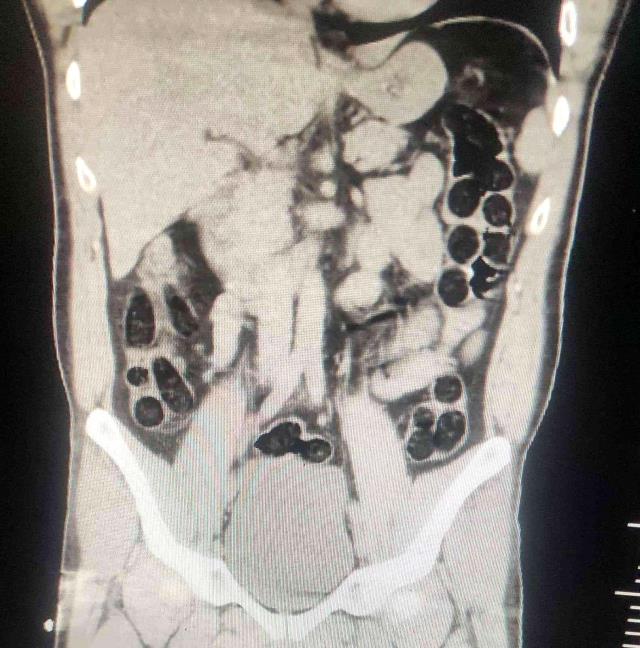

Operasyonda; otobüs ile seyahat eden 2 İran uyruklu şahsın yapılan kontrollerinde ve iç beden muayenesi sonucunda, şahıslardan birinin midesinde 76 paket halinde 714 gram uyuşturucu madde ele geçirildi.